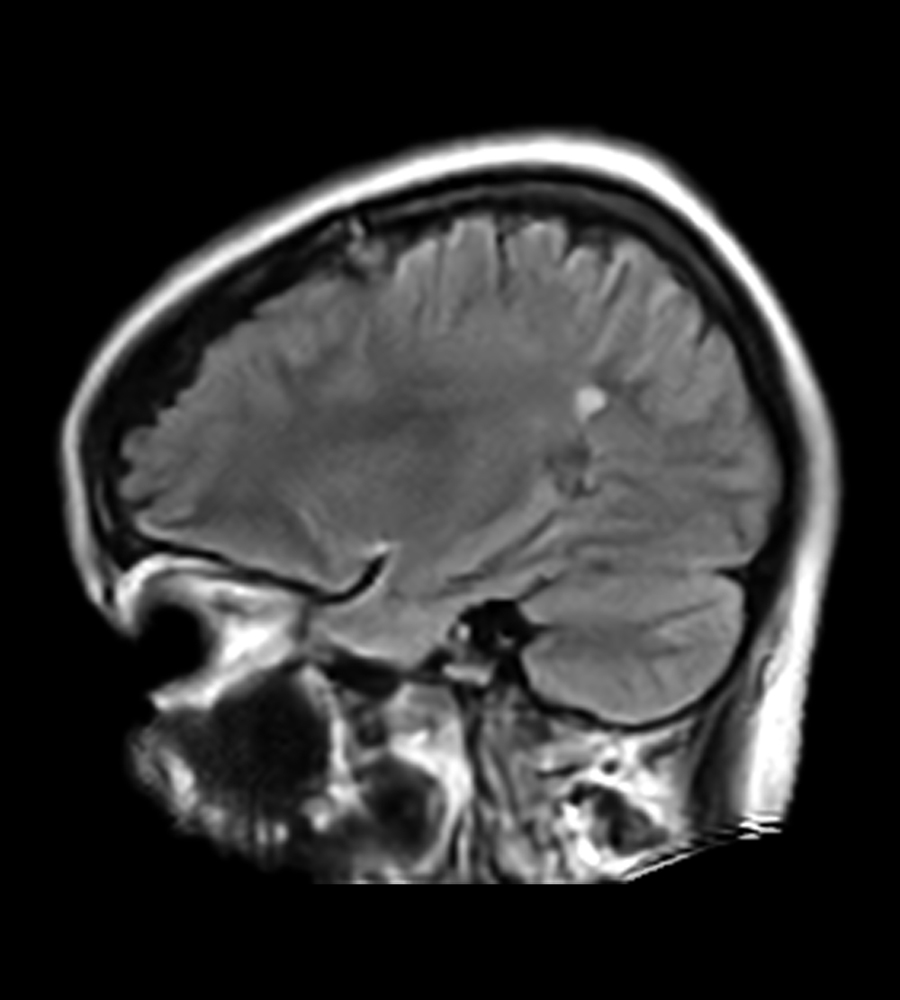

Clinical Images

Clinical Case Types: Headache, Migraine, Multiple Sclerosis, Microvascular Disease, and Tumor Routine Follow-up.

Microvascular Disease